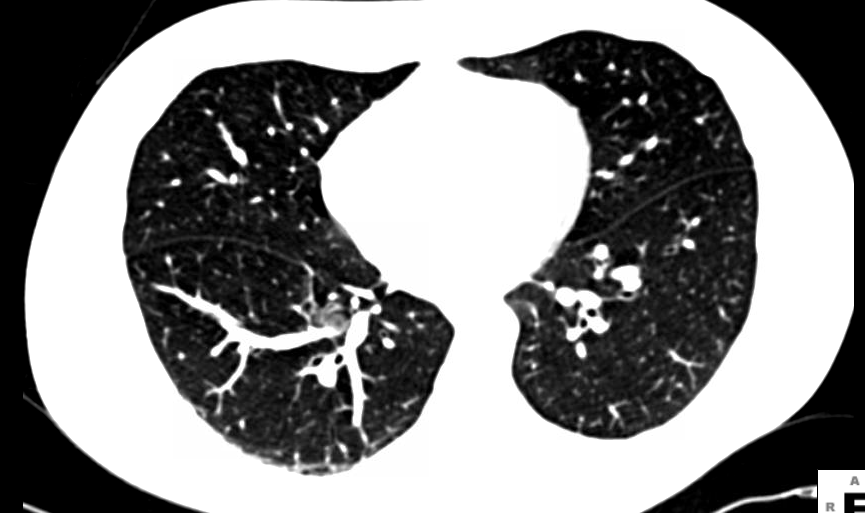

Can Cat Scans Detect Breast Cancer / PET Scans | Breastcancer.org / Are you preparing to have this procedure soon?. By comparing ct scans done over time, doctors can see how a tumor is responding to treatment or find out if the cancer has come back after treatment. This tracer can help identify areas of cancer that an mri or ct scan may not show. Bone scans, positron emission tomography (pet), and computed tomography (ct) all continue to be employed alone or in combination for the detection of breast cancers suspected to have spread. How do ct scans work? However, multidetector computed tomography (ct) often provides the first images of the breast when scanning is performed for pulmonary or cardiac disease.

Learn more about it on our blog. In some cases, physicians use all three imaging techniques. However, multidetector computed tomography (ct) often provides the first images of the breast when scanning is performed for pulmonary or cardiac disease. Ct scans can produce false negatives and false positives. Various imaging procedures are used to diagnose breast cancer, including: Did lucy's cat detect cancer? They may also use it to learn more about the cancer after they find it. So far, researchers at the university have. Sandy,i asked my onc.he says ct's can pick up breast cancer depending part on location.i guess it's like real estate,location,location,location,lol.but seriously theradiologist who read my lung ct in november wrote in his report specifically there was no evidence of breast cancer.i guess due to them watching a lymph gland for 2 years on my rt breast.it was fine in mammogram in october so i am now back to yearly,thank god,andib In some instances, cancers may not show on the scan. When the doctor knows this, they can choose the best course of treatment and maybe even predict your chances of recovery. For breast cancer, these can include computed tomography (ct or cat) scans and positron emission tomography (pet) scans, this technology offers advanced motion management capabilities and may detect lesions as small as 2.8 millimeters, as well as bone scans to find out if the cancer has spread to the bone, identifying abnormal activity and the. The answer is yes, and american health imaging can help.

Clinical impact of 18F-FDG PET/CT on initial staging and ... from www.spandidos-publications.com With cancer cells, they appear as bright spots due to its higher metabolic rate compared to normal cells. Doctors often use ct scans to help them guide a needle to remove a small piece of tissue. Mammography is currently the preferred examination for breast cancer screening; To determine whether the cancer has spread to the lymph nodes to determine whether the cancer has spread to other parts of the body, and if so, where (metastatic breast cancer) A breast positron emission tomography (pet) scan is an imaging test that uses a radioactive substance (called a tracer) to look for breast cancer. If you have more tests, your risk increases. Radioactive material is injected into the body and collects in areas with cancer. For breast cancer, these can include computed tomography (ct or cat) scans and positron emission tomography (pet) scans , as well as bone scans to find out if the cancer.

In some cases, physicians use all three imaging techniques. Mammography is currently the preferred examination for breast cancer screening; Various imaging procedures are used to diagnose breast cancer, including: The specialized cone beam breast ct (cbbct) scanner, developed by boone and colleagues, uses the same amount of radiation as a conventional mammogram. Ct scans can produce false negatives and false positives. Pet scans can be useful for evaluating people after breast cancer has already been diagnosed, in a number of different ways: If your symptoms or other findings suggest that the cancer could be more advanced, however, you may need to have ct scans of the head, chest, and/or abdomen. Not necessarily is the whole body going to be scanned at that time. Identify the correct area for. This can increase your risk of cancer. A pelvic ct scan can be used to detect several types of cancer. Did lucy's cat detect cancer? These scans use large amounts of radiation.